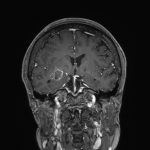

694

'25年11月

90代

頭蓋咽頭腫

頭蓋内腫瘍摘出術

No.’25_96 手術前1

No.’25_96 手術前2